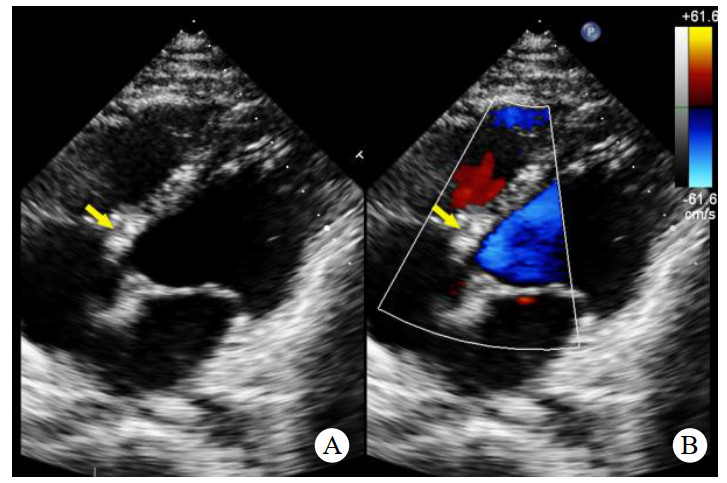

辅助检查如下。实验室检查:高敏C反应蛋白(hs-CRP)和红细胞沉降率(erythrocyte sedimentation rate, ESR)轻度升高。心电图:正常窦性心律,无ST段异常改变。胸部CT:双侧肺门中心对称分布的斑片状高密度影,部分实变,伴空气支气管征,病变边缘模糊。超声心动图:二维超声(2D)主动脉短轴切面显示右乏氏窦瘤破裂(ruptured of ASV, RASV),破入右心房形成“囊袋状”结构,长约1.7 cm,基底部破口内径约0.8 cm(图 1A)。彩色多普勒(color Doppler flow imaging, CDFI)显示全心动周期的左向右分流(图 1B)。连续多普勒(continuous doppler, CW)测得连续分流。室间隔内见4.0 cm×0.7 cm无回声区(图 2A),CDFI显示彩色血流信号随心动周期进出该无回声区(图 2B),考虑室间隔夹层瘤(dissecting aneurysm of the interventricular septum, DAIS)。实时双平面成像同步显示窦瘤破口与室间隔夹层相延续。应用Philips TrueVue三维(three-dimensional, 3D)超声心动图成像模式直观展示室间隔夹层瘤的立体结构(图 3)。

| 注:A为2D超声显示右乏氏窦瘤破裂(黄色箭头)突向右心房形成“囊袋状”结构;B为CDFI显示窦瘤破裂处自主动脉至右心房的左向右分流束 图 1 2D、CDFI显示主动脉短轴切面右乏氏窦瘤破裂情况 |